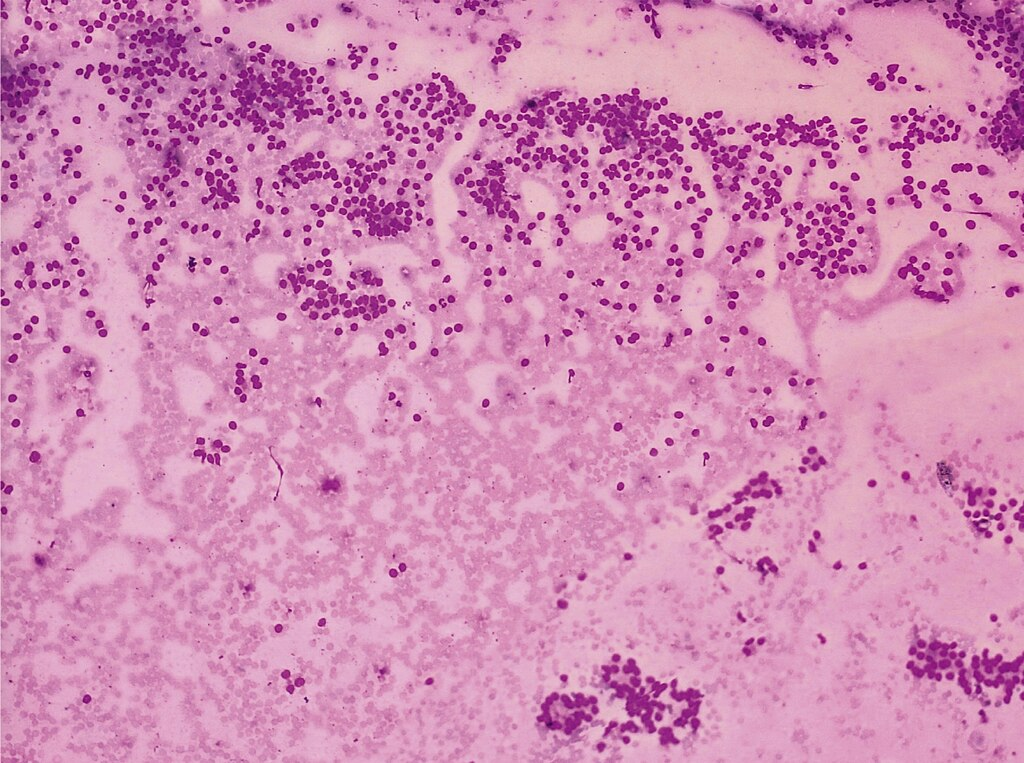

| II | Benign (colloid and follicular cells) | 0 – 3% | Clinical follow-up |